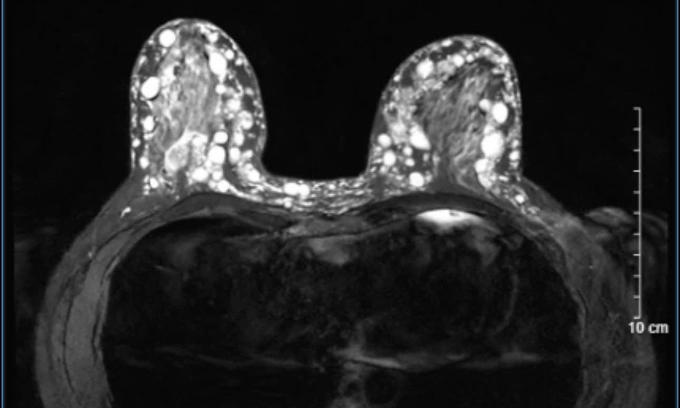

Bác sĩ Hoàng Hồng, Trưởng Khoa Phẫu thuật Tạo hình Thẩm mỹ, Bệnh viện Đại học Y Hà Nội, chẩn đoán bệnh nhân bị u hạt silicon (siliconoma) ở cả hai bên ngực. Các khối u này đã thâm nhiễm toàn bộ tuyến vú, lan rộng ra tổ chức mỡ dưới da, trung bì và sâu tới lớp cân cơ ngực lớn. Nếu trì hoãn, các u hạt sẽ tiếp tục phát triển, gây nguy cơ nhiễm trùng, hoại tử da vùng ngực.

Hình ảnh các hạt sillicone vú trên phim MRI. Ảnh: Bác sĩ cung cấp